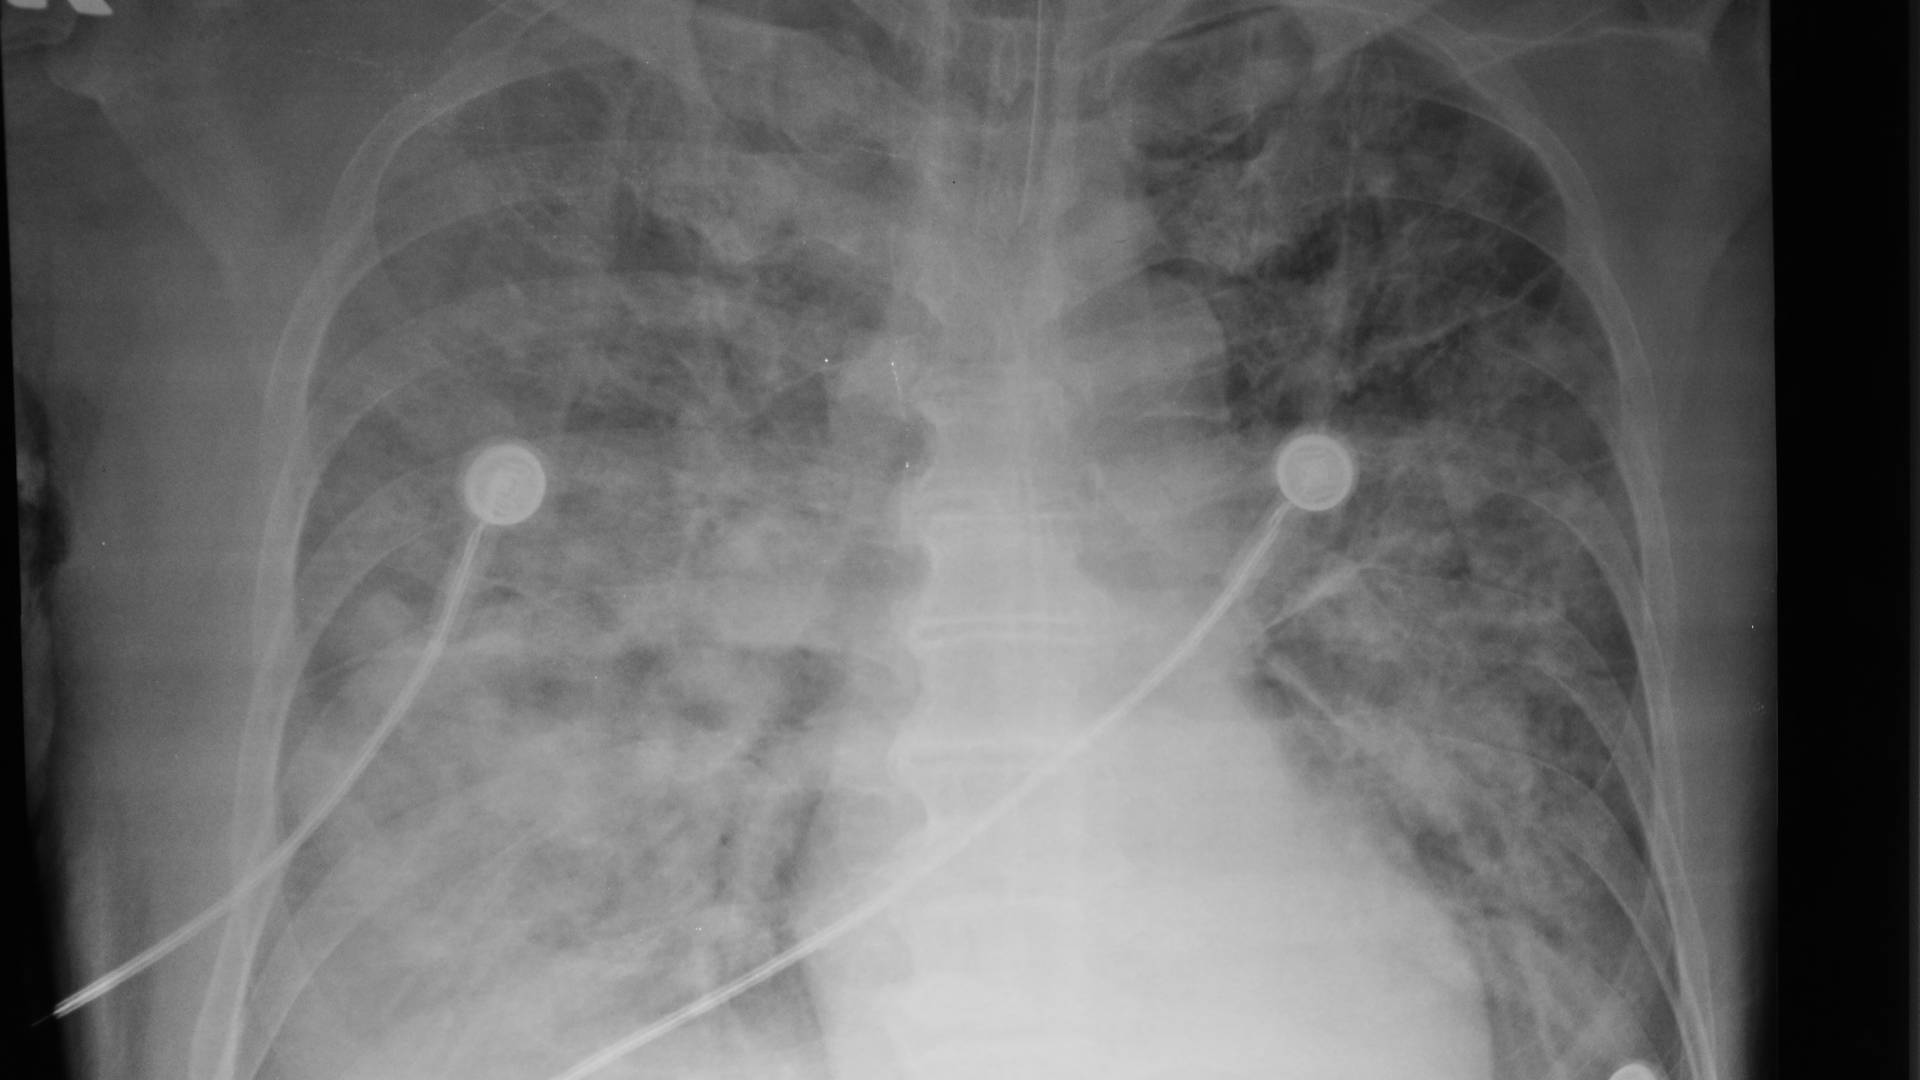

- Adults with acute lung injury (ALI) or ARDS, defined by PaO₂/FiO₂ ≤300 for ALI and ≤200 for ARDS, onset within 36 hours

- Bilateral pulmonary infiltrates on chest imaging not primarily due to left atrial hypertension